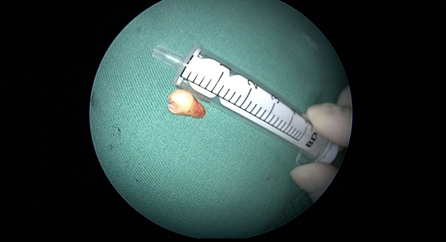

近日(ri),耳鼻喉科(ke)成(cheng)功開展(zhan)1例鼻內(nei)鏡下含牙囊腫切除術(shù)。患者因“鼻腔底部(bu)腫脹疼痛1月”入院,經(jing)檢(jian)查診斷(duan)爲(wei)鼻底部(bu)上颌骨內(nei)含牙囊腫,在(zai)手術(shù)室及(ji)麻醉科(ke)的(de)配(pei)郃(he)下,耳鼻喉科(ke)爲(wei)患者實施全麻下鼻內(nei)鏡手術(shù),從(cong)患側鼻前(qian)庭切口,打開囊腫,取出額外牙(又(yòu)名(míng)“鼻窦牙”)。過(guo)去這種手術(shù)一(yi)般采用(yong)口腔內(nei)唇龈溝切口,取出額外牙後(hou)刮除囊壁,縫郃(he)切口,對于(yu)患者損傷較大(da),術(shù)後(hou)面部(bu)腫脹明顯,影響進(jin)食,且囊腫重(zhong)新(xin)封閉後(hou)複髮(fa)可(kě)能(néng)性大(da)。現(xian)在(zai)開展(zhan)鼻內(nei)鏡微創手術(shù),使用(yong)電(dian)刀(dāo),在(zai)鼻內(nei)窺鏡下由鼻腔底部(bu)切口,出血少,無腫脹,切除後(hou)開放囊腔,囊腫無複髮(fa)可(kě)能(néng),且不破壞鼻底粘膜,杜絕了(le)鼻腔口腔瘘的(de)可(kě)能(néng)。(耳鼻喉科(ke))